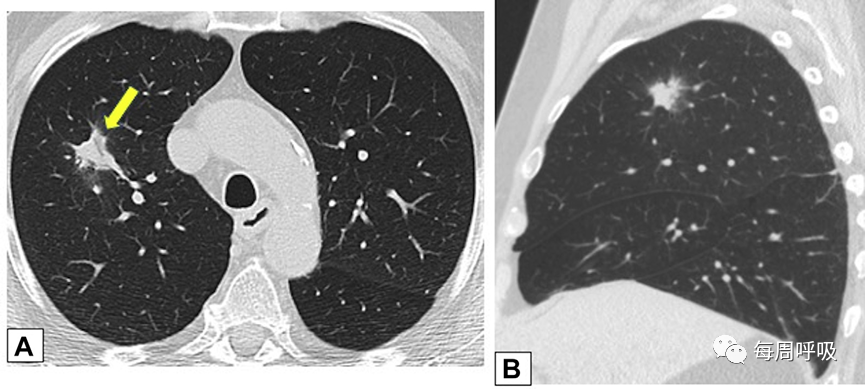

范围从小的微结节(<4mm)(图9)到较大的离散结节(通常达1cm),以及较大的结节或肿块(图10)。后者常被描述为具有不规则或锐利边缘,通常包含支气管充气征(图11)。结节可以单发或多发,通常为实性结节或部分实性结节(图12)。虽然PET扫描对这些病变的评估显示标准化摄取值轻微升高,但结果是非特异性的,临床价值有限(图13、14)。不常见的OP类型为小结节型,包括弥漫性小叶中心型模糊结节(如在非纤维性过敏性肺炎[HP]病例中可见)和树芽征,提示细支气管感染和/或炎症。

图9 微小结节。同一患者的高分辨率CT轴位扫描切面(A)和最大密度投影图像(B)。CT扫描图像显示双肺多发小实性结节,提示可能的恶性肿瘤或感染。CT扫描引导下的针吸活检结果与机化性肺炎的诊断一致。

图10 肿块42岁的患者,病态肥胖,有呼吸困难,右肺上叶(A)和右肺下叶(B)的轴位CT平扫图像显示双侧,胸膜下或周围肿块样实变区域。这些发现是非特异性的;活检结果提示机化性肺炎,类固醇治疗后消退。

图11 支气管充气征。一名接受美沙拉嗪治疗的38岁男性溃疡性结肠炎患者出现气促。A,后外侧胸片显示双肺多发结节。胸部CT轴位(B)和冠状位(C)增强扫描显示结节周围和支气管血管周围,一些伴有气道扩张(B和C中的箭头)。粗针穿刺活检结果与机化性肺炎相符。

图12 孤立性结节。一名73岁男性吸烟者低剂量CT。轴位(A)和矢状位(B)平扫图像显示右肺上叶孤立的不规则结节影,伴有细微的气道扩张(箭头在A)。支气管内超声引导下细针活检结果符合局灶性机化性肺炎。